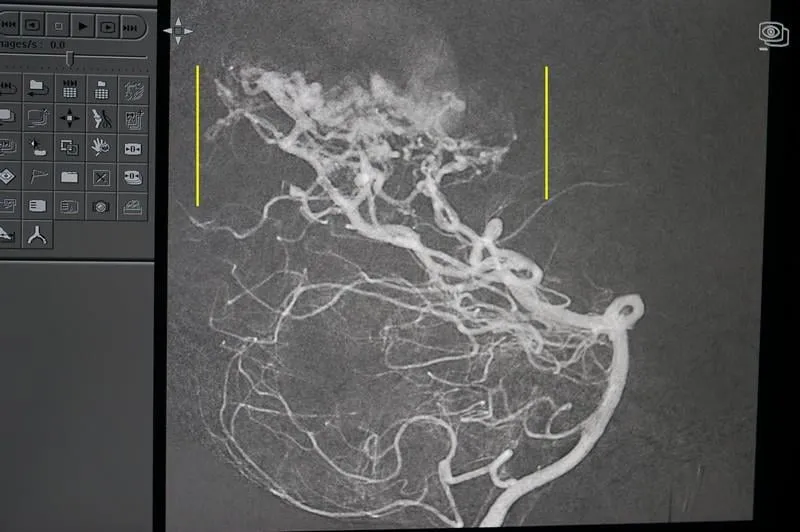

Medisite a assisté à une intervention au service de NRI de la Fondation Rothschild. Il s’agissait d’une femme de 49 ans qui souffrait d’une malformation artério-veineuse cérébrale. Ce type de malformation se traduit par une absence de capillaires sanguins entre une veine et une artère. Les veines sont dans ce cas directement branchées sur les artères et risquent donc de se rompre, entraînant une hémorragie cérébrale. Les veines sont en effet plus fragiles que les artères et ne supportent pas la puissance du débit sanguin artériel.

Le rôle du médecin est de réparer cette malformation en bouchant la liaison veine-artère avec des colles biologiques pour exclure de la circulation sanguine la zone pathologique et dissiper le risque hémorragique.

Sur la photo : la malformation, encadrée par les deux lignes jaunes, ressemble à une pelote de vaisseaux tortueux. Cet amas est appelé nidus.